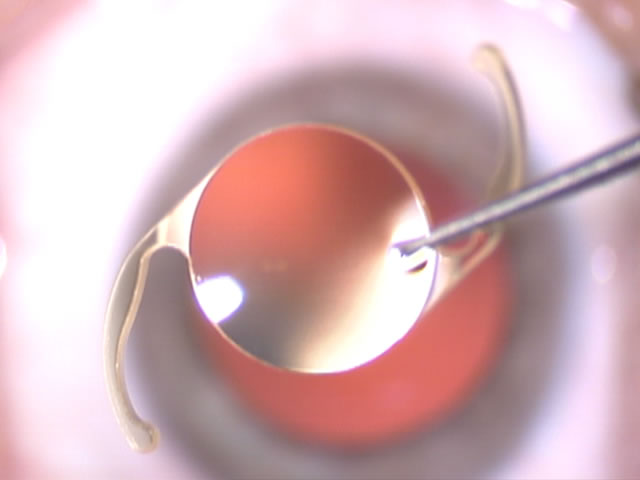

Presso il proprio studio di Gussago (Brescia), il dottor oculista Giovanni Coen esegue interventi di chirurgia refrattiva con impianto di lenti intraoculari asferiche Premium: una soluzione che permette la correzione dei difetti del cristallino (la seconda lente dell'occhio, situata internamente rispetto alla cornea) che, spesso anche per l'avanzare dell'età, perde la propria trasparenza causando una visione poco nitida e non definita. La microchirurgia del cristallino offre risultati eccellenti anche in presenza di cataratta e consente di eliminare difetti come la miopia, l'ipermetropia, la presbiopia e l'astigmatismo.

L'intervento consiste nella sostituzione, mediante laser, del cristallino danneggiato con lenti intraoculari artificiali mono o multifocali personalizzate, che garantiscono una visione perfettamente limpida, ad alto contrasto e priva di difetti. Il trattamento chirurgico è indolore anche nel post intervento, avviene tramite anestesia topica in gocce e permette l'immediata ripresa delle attività quotidiane in sole 24 ore.